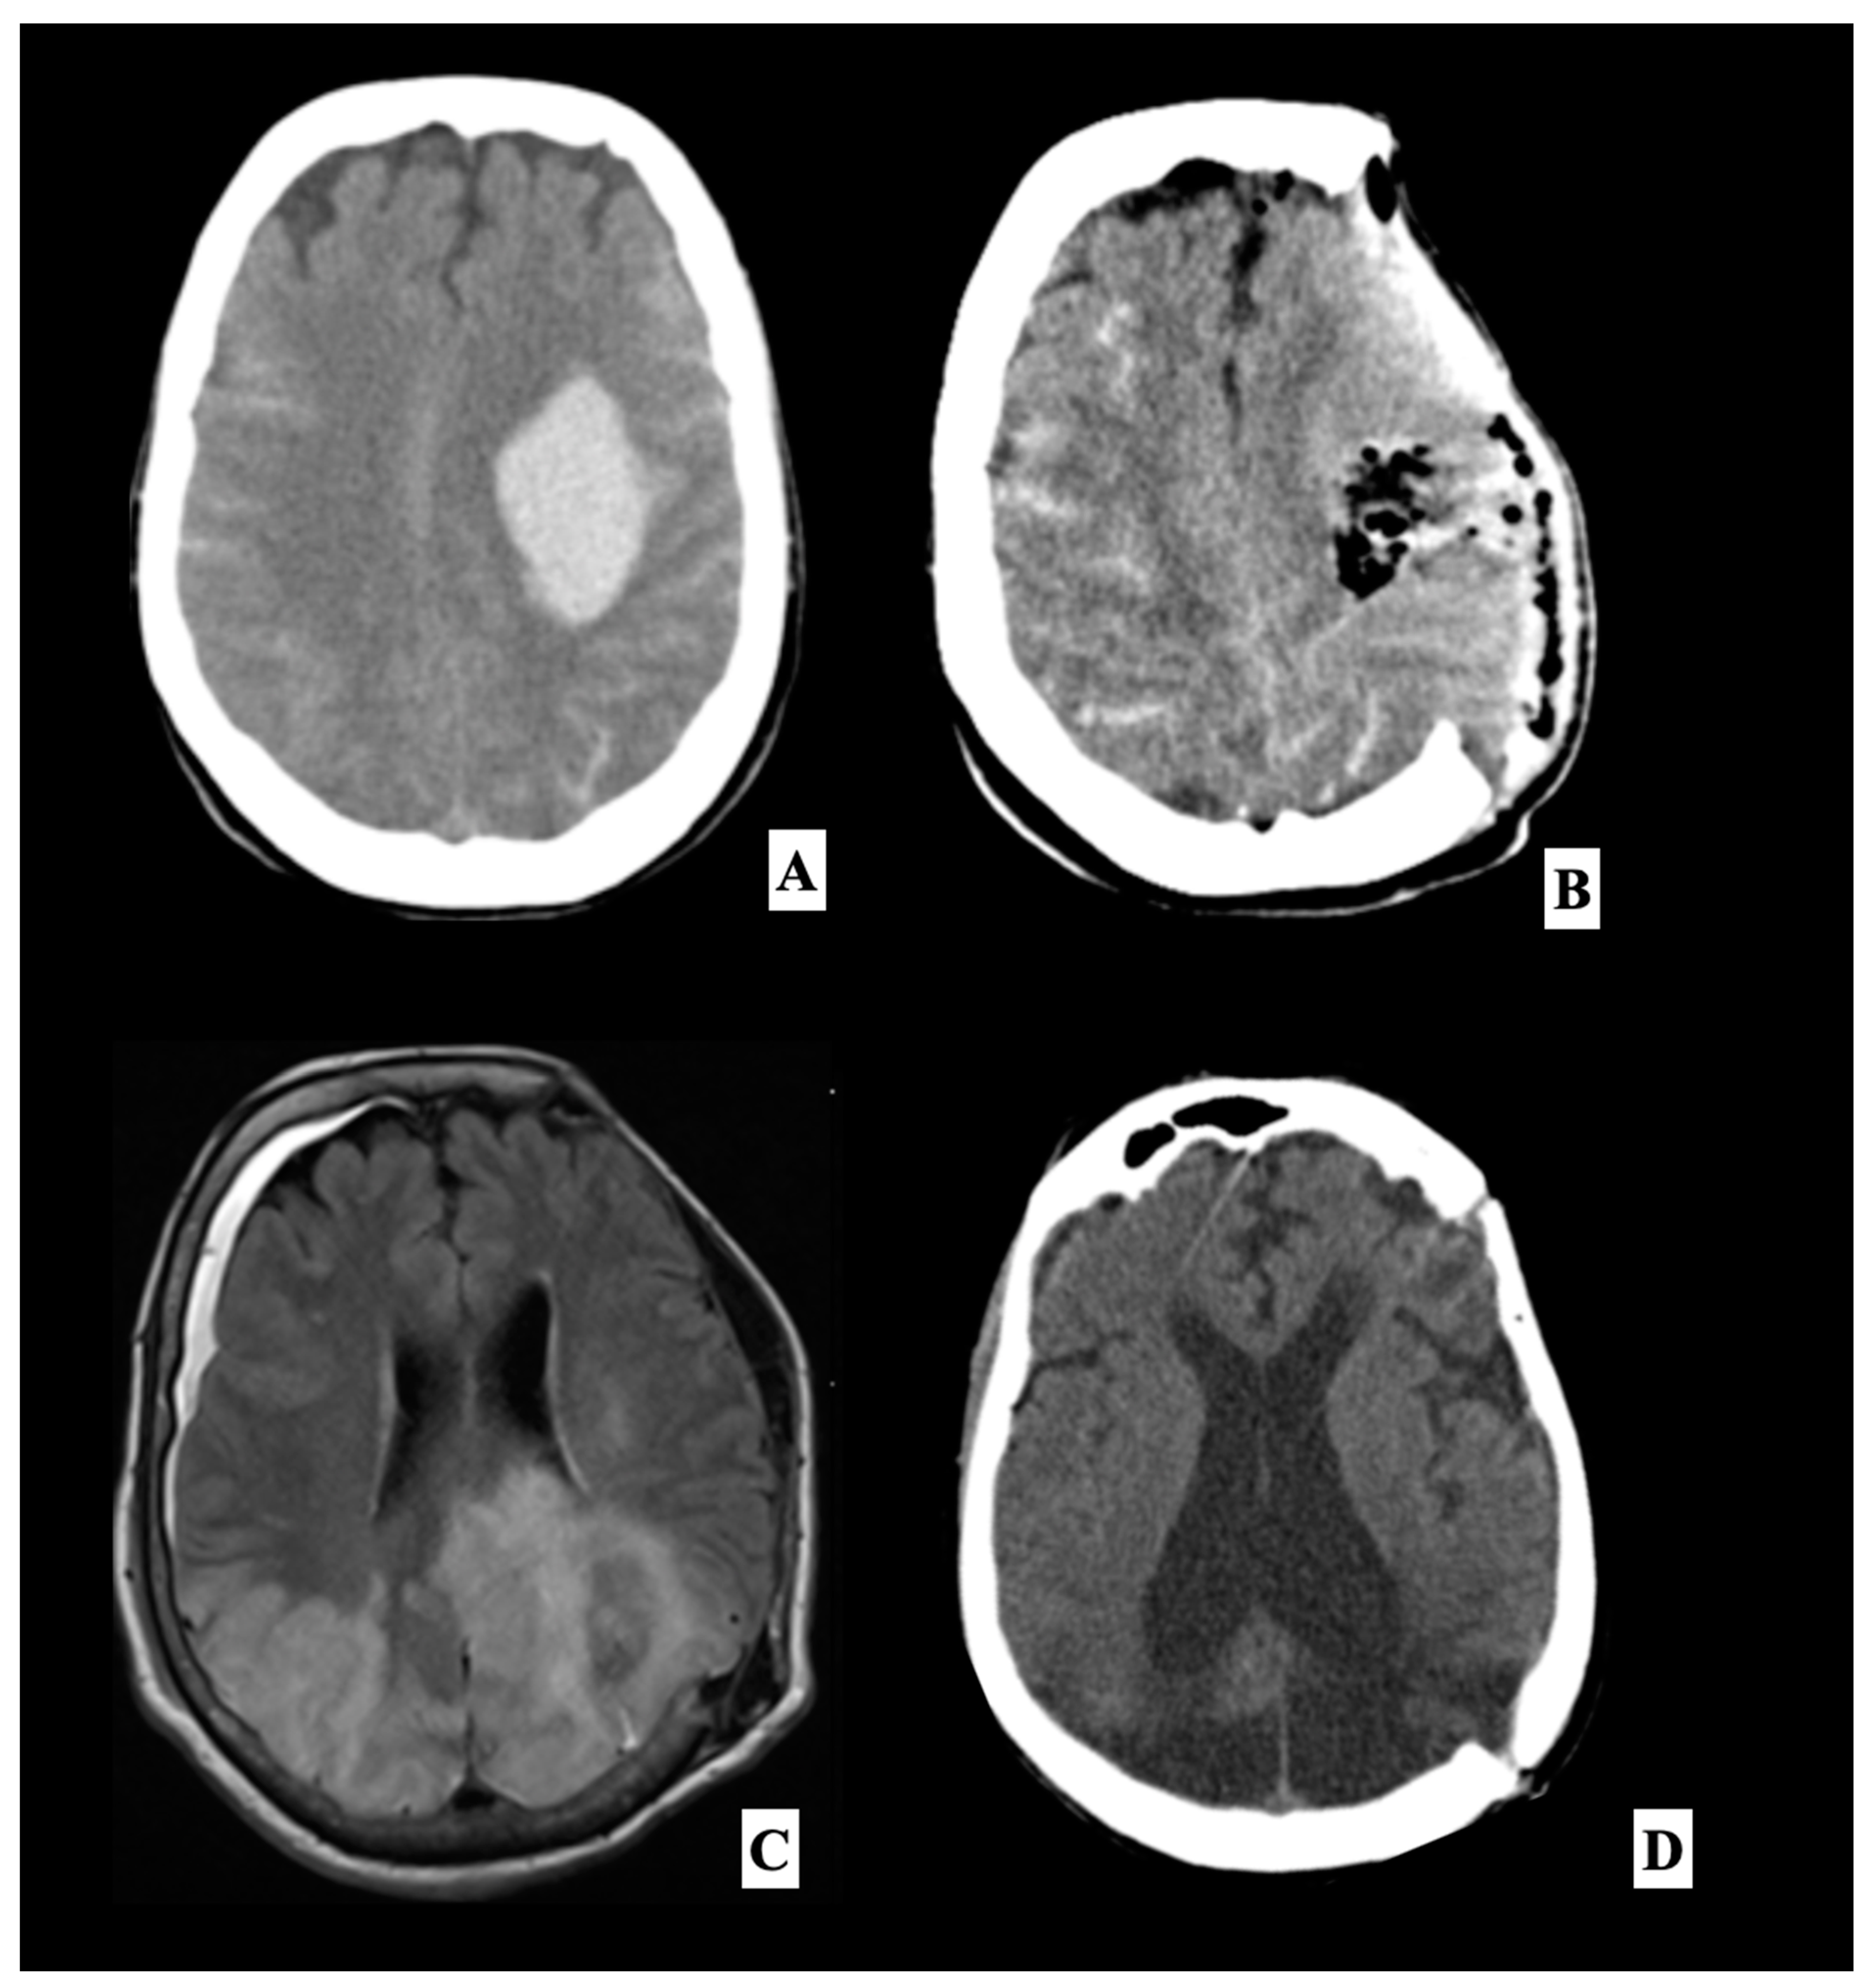

| 47 | Our cases | 2020 | 1 | 55 | F | Hypertension | Intraparenchymal spontaneous hemorrhage | No | 21 | Seizure | 42 | Stable | Hydrocephalus 4 weeks after surgery |